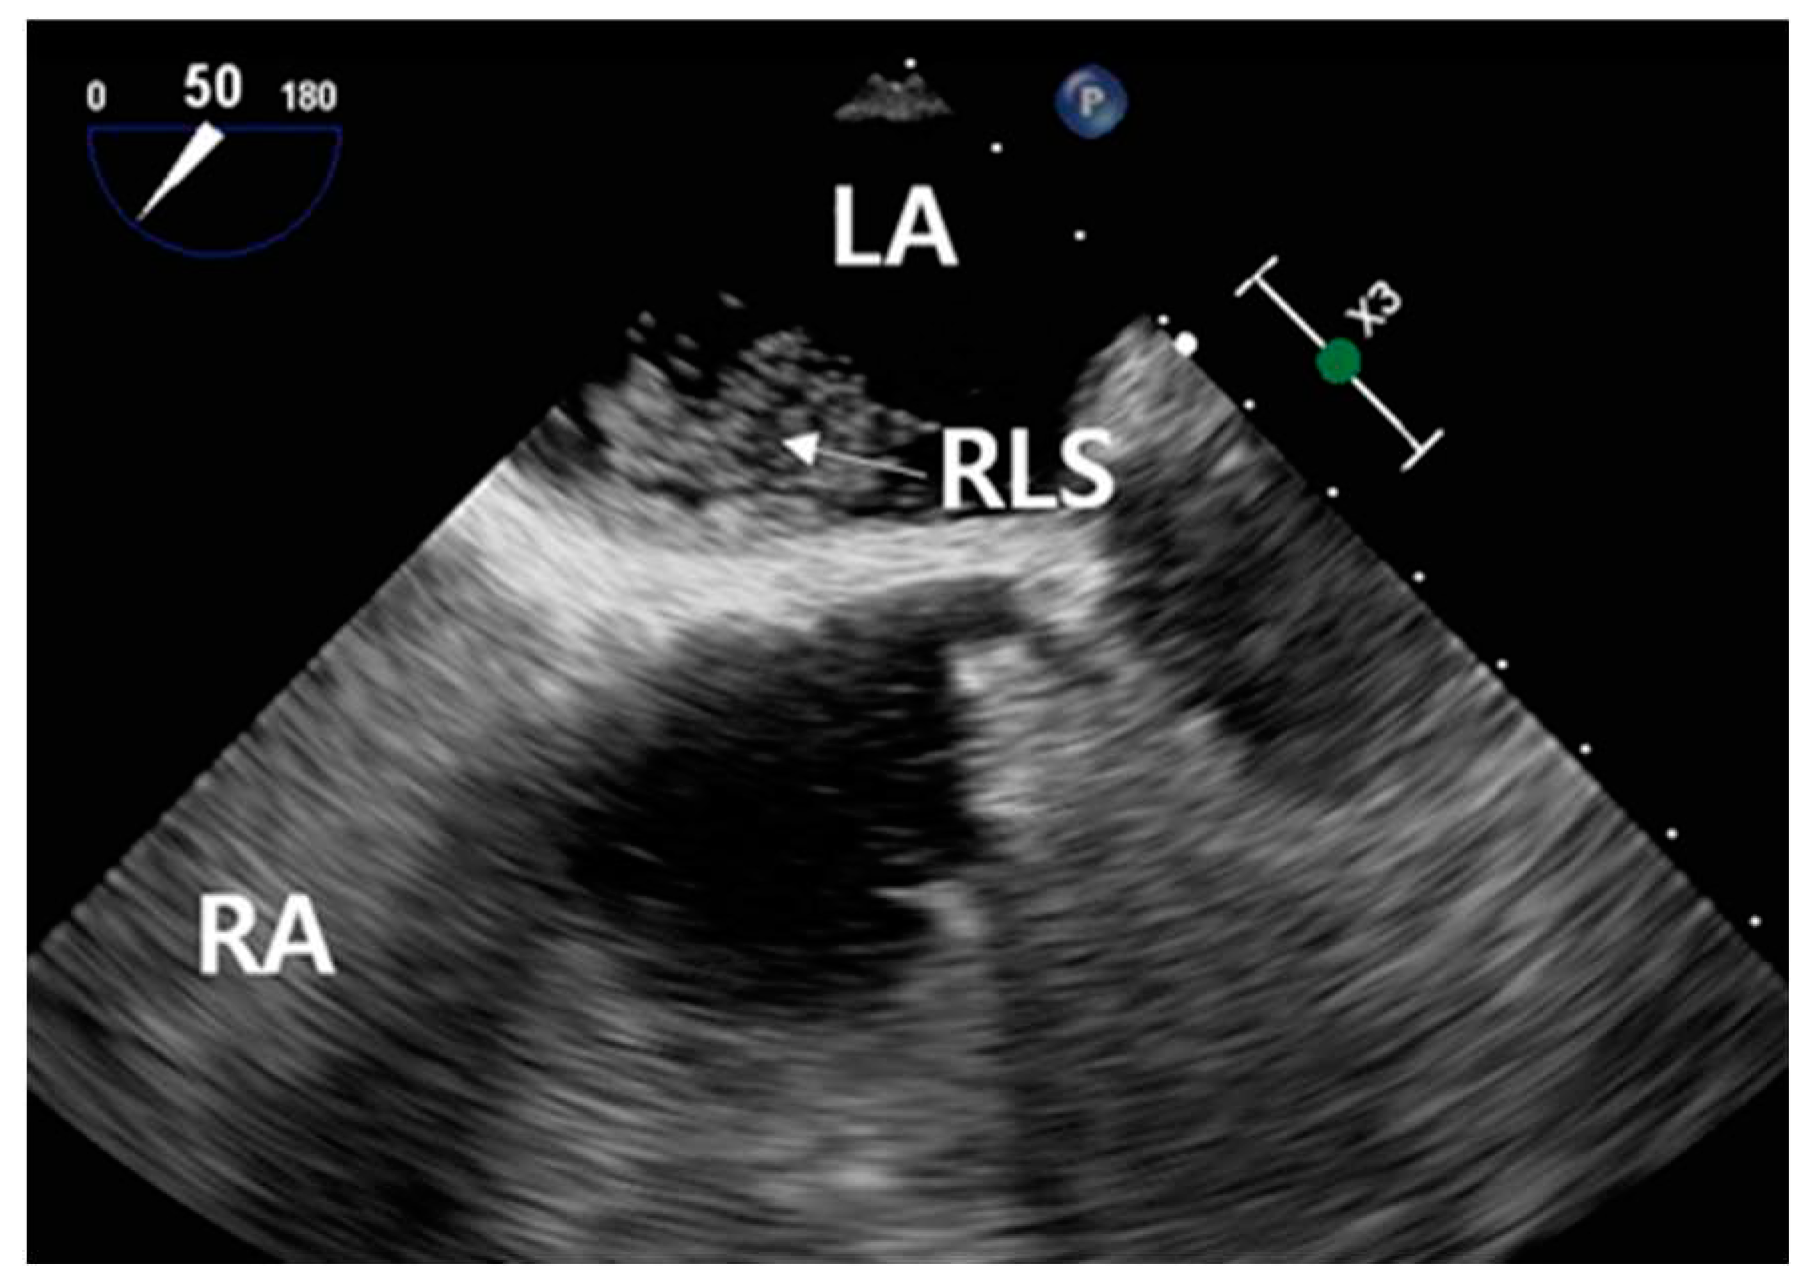

Contrast-enhanced TEE assessed the morphology of PFO and timing of RLS. TEE employed an ultrasound machine (Affiniti 70C, Philips, USA) and a probe (X7-2t, Philips, USA), which were operated by a cardiologist. A manufactured bubble contrast agent enhanced the images. TEE revealed a PFO diameter of approximately 8 mm, a tunnel length of approximately 21 mm, and a hypermobile interatrial septum (Figure 6).

Figure 6. TEE view of measured PFO diameter and tunnel length.